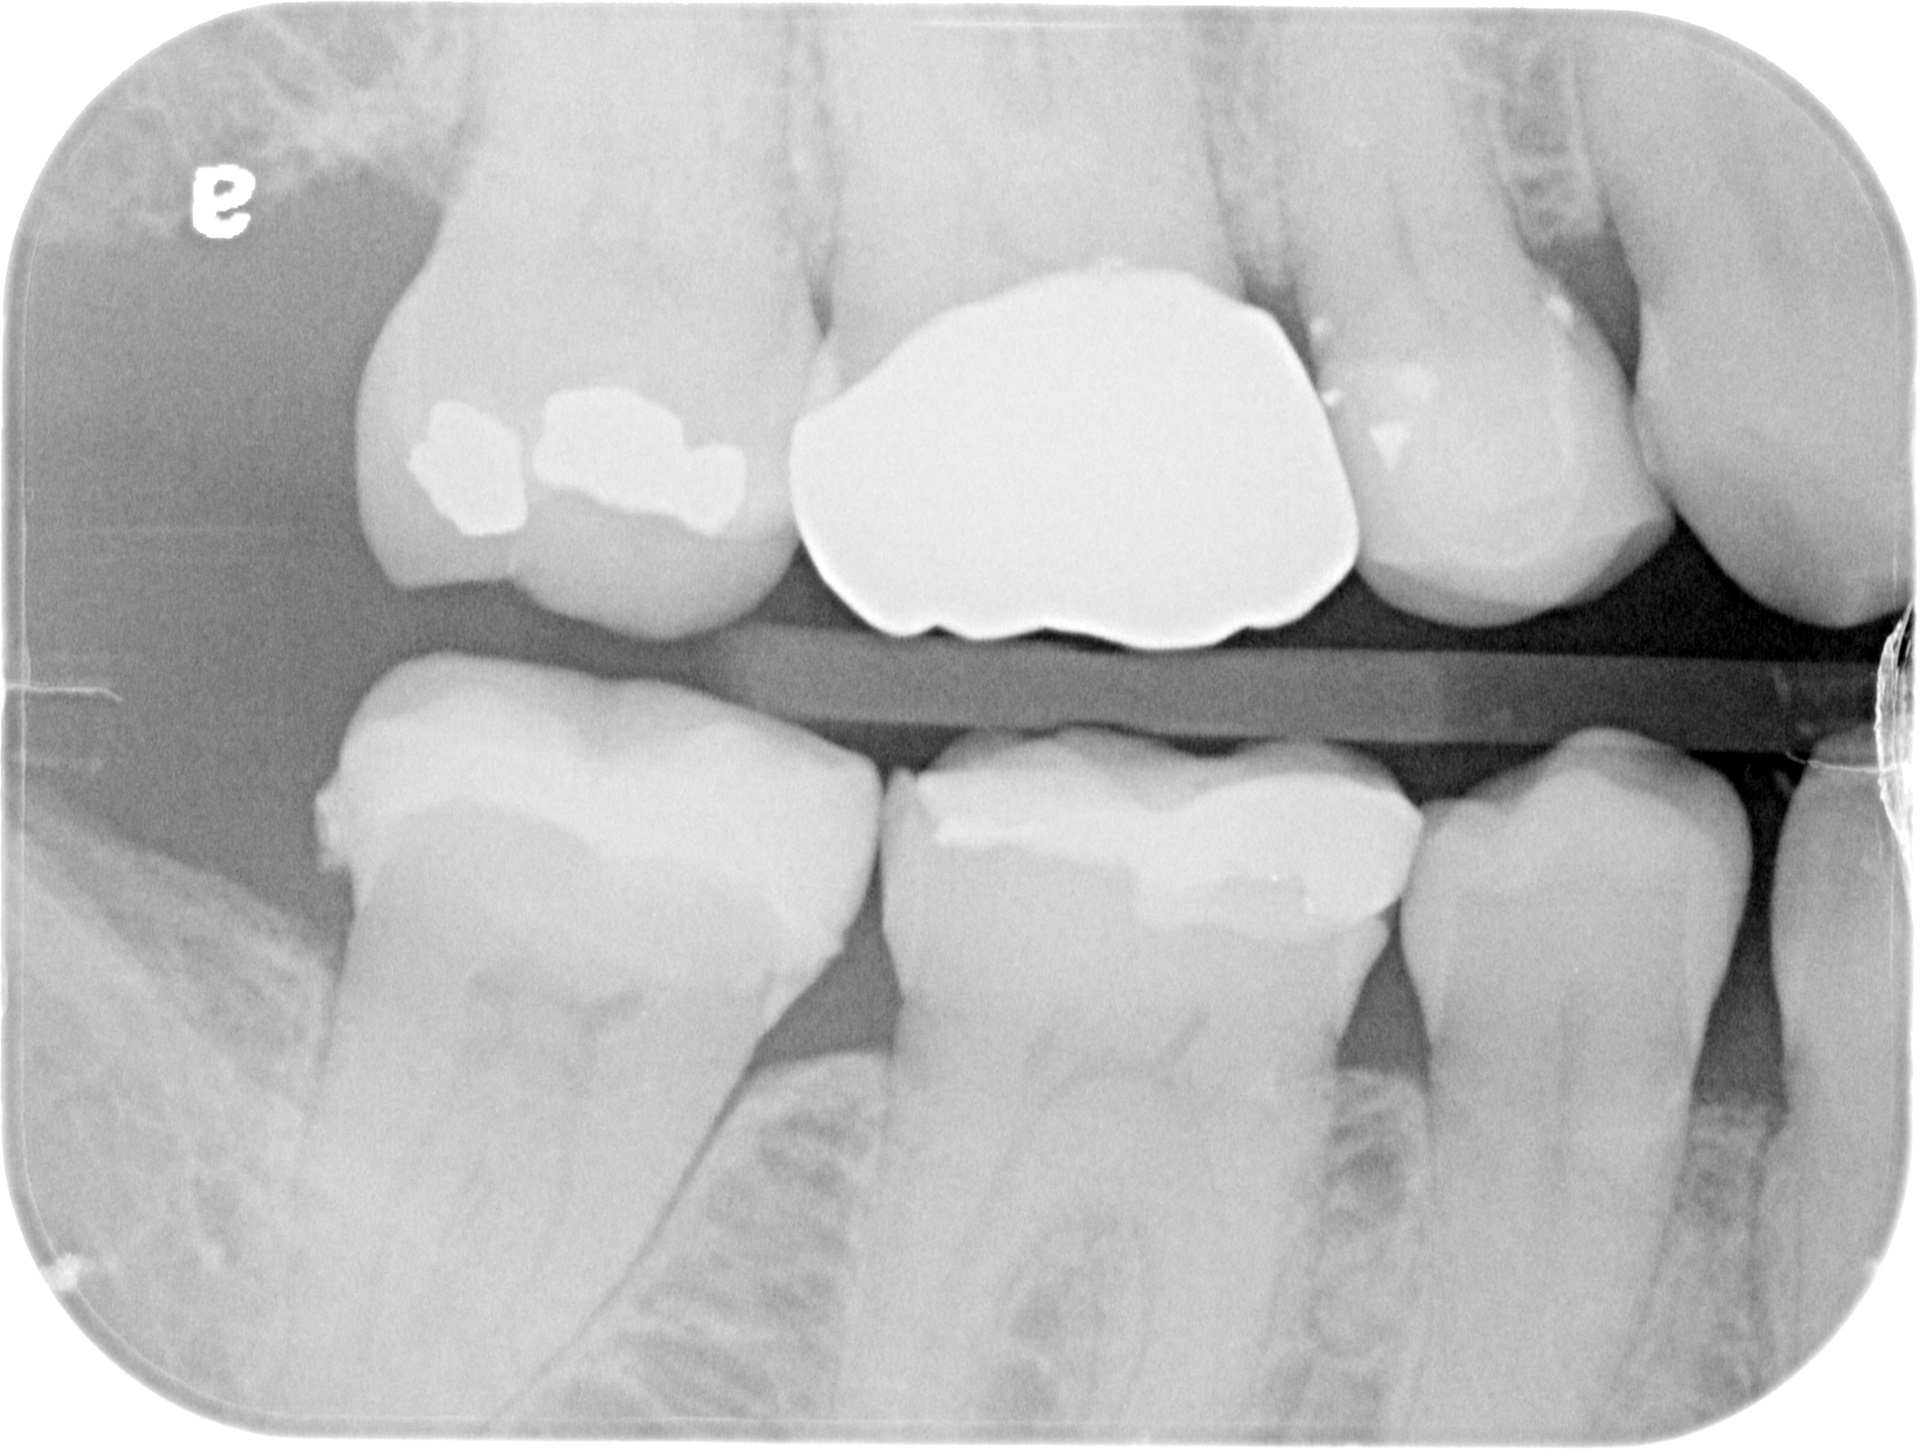

15 post-op bitewing